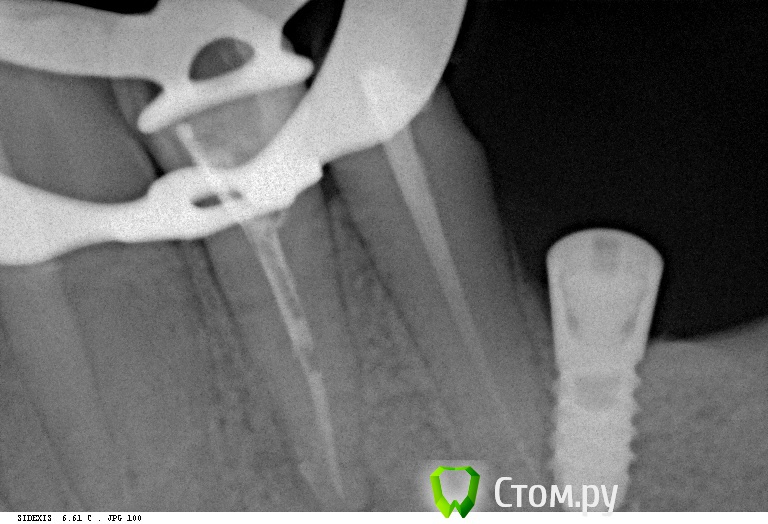

bullbull Опубликовано 20 ноября, 2013 Поделиться Опубликовано 20 ноября, 2013 Вот это имплантат по касательной! На первых двух фото 2011 год (винт установлен 2008-2009). На последнем фото пара недель назад перед удалением зуба. В лунке пальпируется верхушка винта. Удалять железо не хочет, так как ничего не беспокоит. Ссылка на комментарий